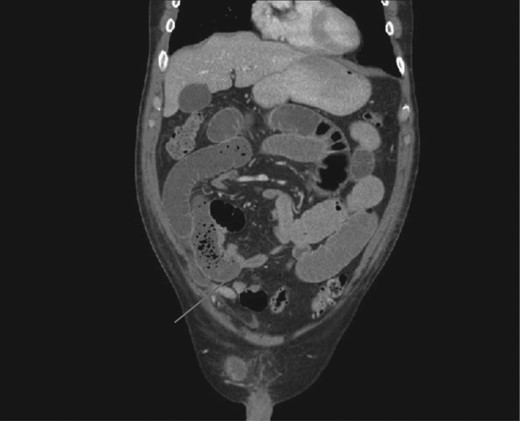

The patient presented to the emergency department on post-operative Day 3 with complaints of nausea, vomiting, abdominal distention and obstipation. Physical examination revealed a tender and distended abdomen, further evaluation with cross-sectional imaging revealed a transition point in the right lower (Fig. 1). He subsequently underwent diagnostic laparoscopy where a free end of the barbed suture was noted to be adherent to the small bowel creating a sharp angulation in the bowel leading to obstructive symptoms (Fig. 2). The suture was lysed close to the peritoneum, which led to the relief of bowel obstruction. Post-operatively the patient had return of bowel function the following day and was discharged home.

CT scan demonstrating transition point between dilated proximal and collapsed distal small bowel.